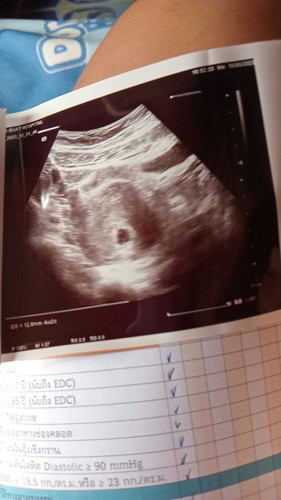

เมื่อวานไปฝากท้องมาค่ะและหมอก็ซาวด์ให้ หมอบอกว่ามีแต่ถุงการตั้งครรภ์แต่ยังไม่มีตัว เรากังวลว่าจะท้องลมมีภาวะเสี่ยงสูงมั้ย แต่บอกก่อนน่ะว่าท้องเราพึ่งได้แค่4week2day หรือว่าท้องเรายังอ่อนเกินไป เราไม่รู้จริงๆ ขอบคุณล่วงหน้าน่ะค่ะ🙏🥰

บ้านนี้ซาวตอน5-6วีคก็เจอแต่ถุงค่ะมาเจอน้องตอน7วีคพร้อมเสียงหัวใจตัวจิ๋วเดียวเองค่ะซาวผ่านช่องคลอดถึงเห็นชัด

10วีค กำลังพอดีค่ะ เจอน้องเจอหัวใจ ตอนนี้ก็ทำใจสบายๆไม่ต้องเครียดค่ะ ช่วงนี้ก็กินโฟลิคกินนมบำรุงด้วยนะคะ